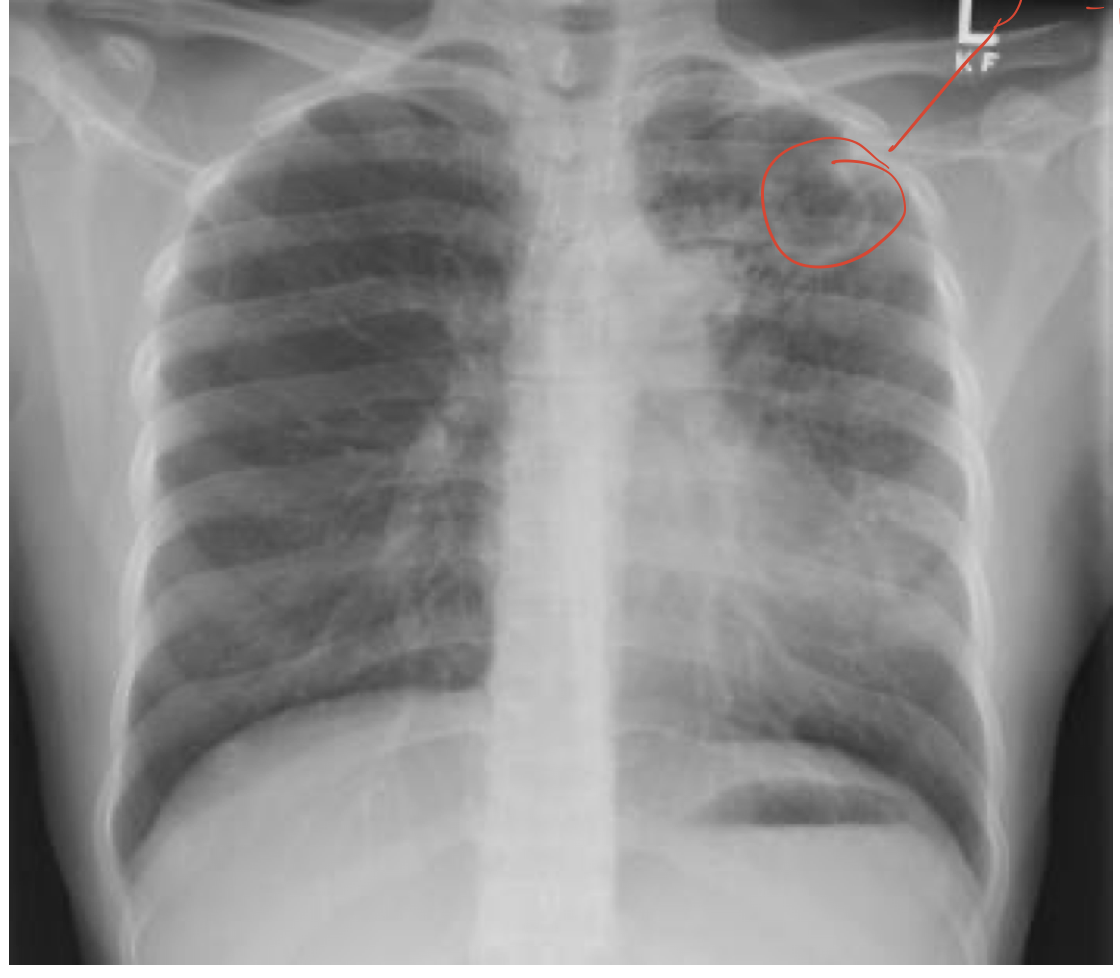

myococavitation

cough, hemotysis, fever, dyspnea, weight loss, night sweats, subacute or chronic presentation. need to do CXR